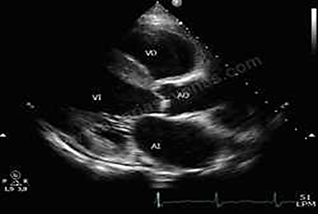

Imagen 3

Ecocardiograma.

Reporte: Ventrículo izquierdo hipertrófico con fracción de eyección conservada y sin alteraciones de la contractilidad segmentaria. Cavidades derechas severamente dilatadas con movimiento paradójico septal, insuficiencia tricúspidea severa.